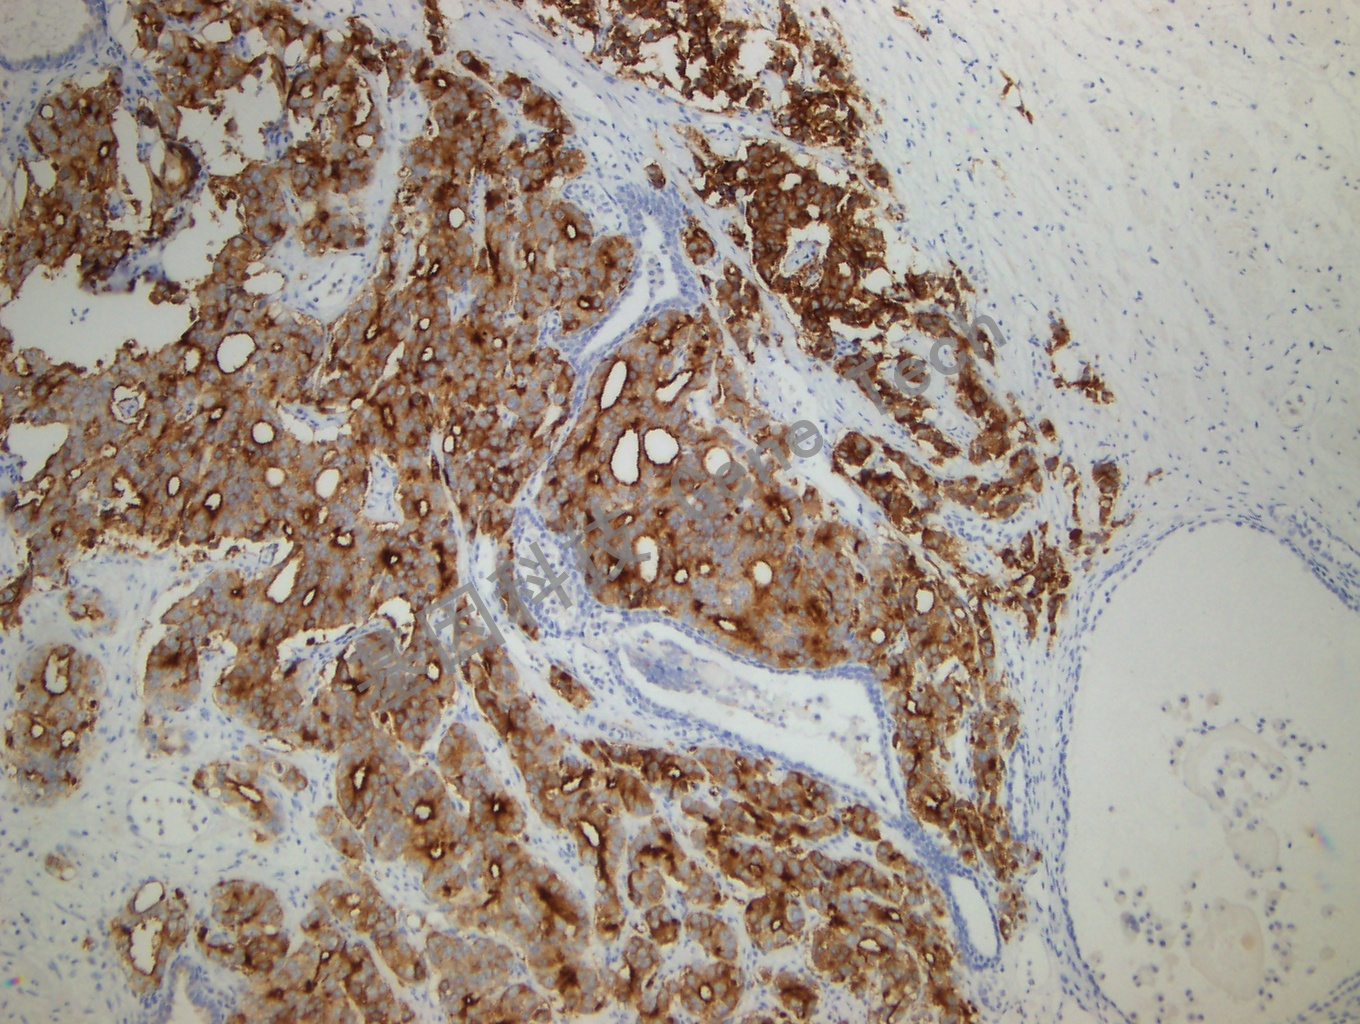

| 預(yù)處理:高pH熱修復(fù) | 陽性部位:細(xì)胞膜/細(xì)胞漿 | 陽性對(duì)照:前列腺癌 |

| 前列腺癌石蠟切片,用 PSMA(GT2051)染色,細(xì)胞膜/細(xì)胞漿陽性,DAB 顯色。 | ||